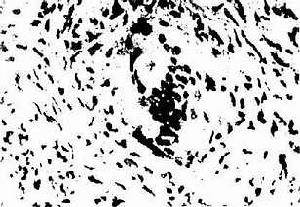

組織胞漿菌孢子經呼吸道吸入,多數被機體防禦機制消滅,到達肺泡的孢子增殖並轉化為酵母型。引起中性粒細胞、巨噬細胞聚集,酵母被巨噬細胞吞噬,但不被殺滅,仍能繁殖並通過肺門淋巴結到達血循環。孢子吸入2~3 周后,隨著細胞免疫的產生,巨噬細胞殺滅真菌。隨炎症反應的增強形成肉芽腫或乾酪樣壞死。免疫功能正常的病人大多數病變局限於肺內,如免疫功能低下或感染菌量過大則可導致進行性播散型組織胞漿菌病。癒合方式為鈣化或纖維化。

肺莢膜組織胞漿菌感染實驗室檢查:1.病原學檢查 痰、纖支鏡刷檢、灌洗液真菌培養4 周以上,菌絲相轉為酵母相,可見其特徵性的齒輪狀孢子。病理學檢查旨在發現病原菌,可用銀染色、PAS 染色等特殊染色,若在巨噬細胞或白細胞中發現似有莢膜的酵母菌有確診價值。採用免疫組化能準確鑑別菌種。播散型病例骨髓、淋巴結、分泌物和活檢組織培養常陽性。